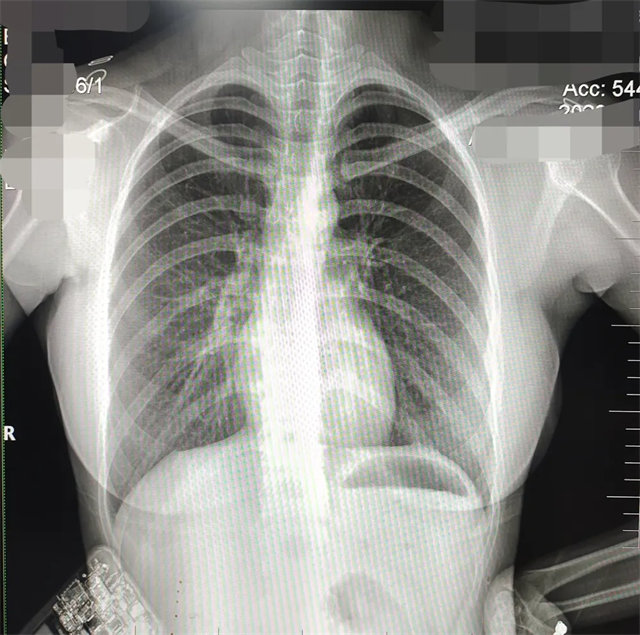

拍攝的不合格胸片的缺陷和解決方法

缺陷:肩胛骨未完全拉離肺野,吸氣不完全,存在金屬偽影遮擋,略有聳肩,且肺尖顯示不好,圖像顆粒感較強(qiáng),管電流量不夠,信噪比偏低。

解決:去除金屬物品后,按標(biāo)準(zhǔn)體位,使患者雙肩旋前與前胸一并緊貼成像件,適當(dāng)調(diào)高mAs,然后深吸氣后屏氣曝光。